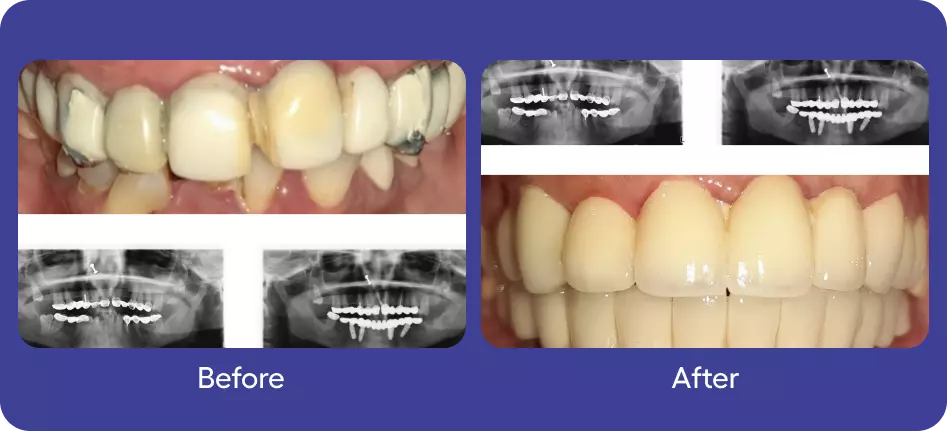

Prosthodontics

Implants

Full Mouth Rehabilitation